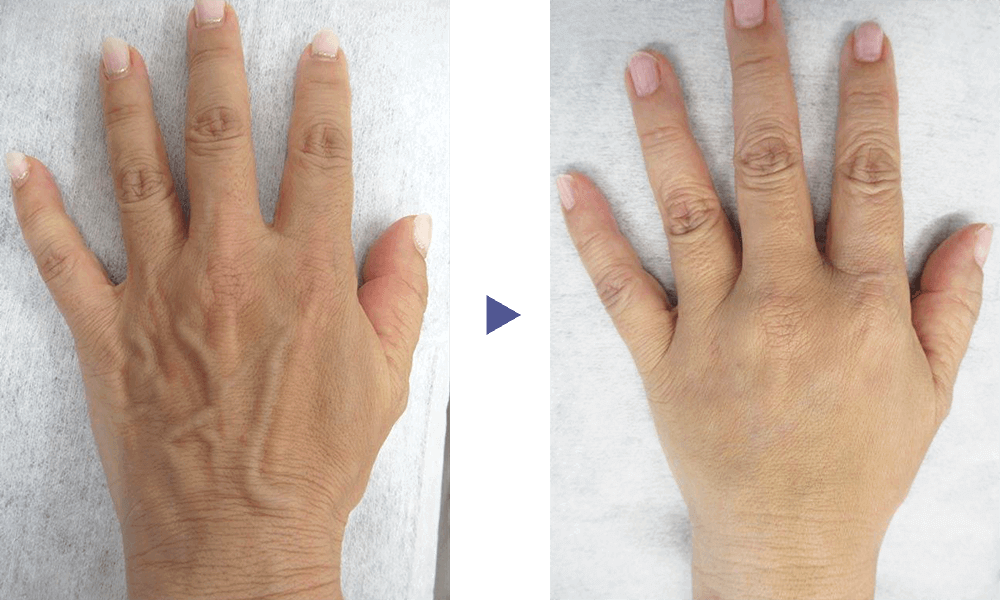

手の甲の血管や、前腕の血管などがボコボコと浮き出る症状を治療します。

硬化療法や血管内レーザーで治療することで、血管を目立たなくする効果が見込めます。

「手(hand)」と「静脈(vein)」を合わせて、「hand vein(ハンドベイン)」と呼びます。 発症すると、手の甲や前腕部の血管が数ミリ〜5ミリ程度に拡張し、こぶのように膨れて目立つため、見映えに影響が出ます。特に、手の甲は日常的に人目につく部位なので、血管が過剰に浮き出ていることを気にして悩んでいる患者様は多くいらっしゃいます。

ハンドベイン自体は病気ではなく、放置していても何らかの健康被害が出るわけではないのですが、加齢による老化と共に症状が進行する特徴があり、10代〜20代では目立たなかったはずの血管が目立つようになり、若々しさを欠いた、年老いた印象の手・前腕になってしまうのです。

ハンドベインの治療方法は、具体的には以下の4つが挙げられます。 なお、当クリニックでは患者様の体への負担が少ない硬化療法と血管内レーザーをおすすめしております。

硬化療法は、血管の中に硬化剤と呼ばれる薬剤を注入し、血管に炎症を起こさせて、閉塞させることで症状の改善を図る術式です。 体外照射タイプのレーザーを用いるよりも、より太い血管を処理できます。 注射による施術であるため、体への負担が少なく、比較的簡単に行うことができる施術であるという特徴があります。 硬化療法は下肢静脈瘤の治療に広く用いられている術式となっており、多くの患者様にご提案している手法です。

血管内レーザー治療とは、血管内にレーザーファイバーのカテーテルを挿入して、レーザーの熱で静脈を焼いて縮小させる術式です。 下肢静脈瘤での治療実績を持つ方法であり、前腕部の直線的な長い静脈を処理する場合に適しています。 ただし、手の甲などの複雑な形状の血管にはあまり向かないため、硬化療法と併用する場合もあります。

ハンドベインの治療は、メスを用いた大掛かりな手術などを行う必要がないため、術後の生活に大きな制限が出るようなことはありません。 また、硬化療法や血管内レーザー治療を行った血管が、再び膨れてくるというケースはほとんどないです。 ただし、治療した静脈血管以外の部分が目立ってくる場合がありますので、その際には新たに治療が必要となります。

ハンドベインの治療では、大掛かりな切開が必要な手術などを行うわけではないため、術後の生活に大きな支障が出ることはありません。 治療は当日に完了できるので入院などの必要もなく、多少の腫れや痛みなどのダウンタイムはあるものの、1週間程度で経過と共に自然に治っていきます。